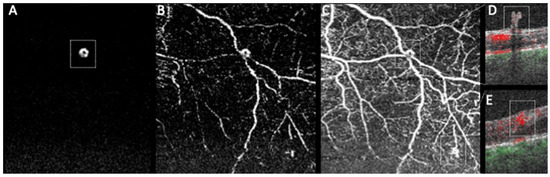

- Vaz-Pereira, S.; Silva, J.J.; Freund, K.B.; Engelbert, M. Optical coherence tomography angiography features of neovascularization in proliferative diabetic retinopathy. Clin. Ophthalmol. 2020, 14, 3351–3362. [Google Scholar] [CrossRef] [PubMed]